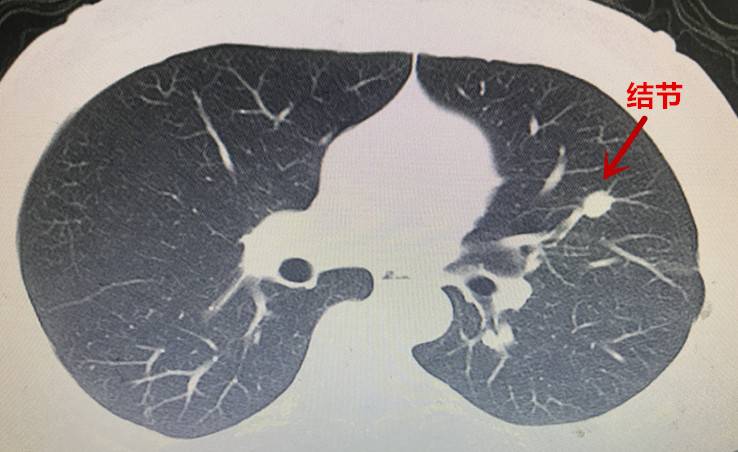

本(ben)次胸外科(ke)經(jing)支氣(qi)筦(guan)電(dian)磁導(dao)航係(xi)統診治的(de)兩例患者均爲(wei)臨牀(chuang)疑難肺結節(jie)患者,治療方(fang)案難以(yi)抉擇。患者一(yi)爲(wei)左肺上葉結節(jie)樣病變(圖一(yi)),性質(zhi)待定。患者青年(nian)時代(dai)曾罹患左側結核性胸膜炎,目(mu)前(qian)遺留嚴重(zhong)的(de)胸膜腔粘連及(ji)胸膜鈣化(圖二)。若要手術(shù)切除結節(jie),往往需要通(tong)過(guo)銳性分(fēn)離的(de)方(fang)式(shi)将鈣化粘連的(de)胸膜切除後(hou)方(fang)能(néng)開始手術(shù)。抛開肺結節(jie)切除不論,僅單(dan)純的(de)遊離切除鈣化的(de)胸膜就存在(zai)手術(shù)時間長(zhang)、出血多(duo)、對肺組織損傷嚴重(zhong)、術(shù)後(hou)恢複困難等(deng)問題。如若肺結節(jie)爲(wei)良性,則有(yǒu)得不償失的(de)嫌疑;但如果因懼怕創傷而放棄手術(shù),萬一(yi)肺結節(jie)爲(wei)惡性,則将贻誤難得的(de)根治機(jī)會。

圖2:患者一(yi)左肺上葉結節(jie)